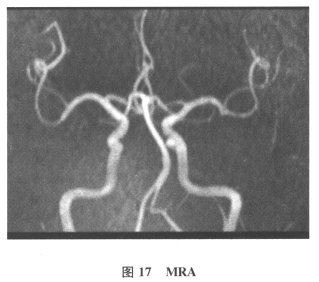

[多选题]患者男,61岁。因“发作性头晕2年,加重伴记忆力下降、走路不稳3月余”就诊。查体:BP140/70mmHg;意识清楚,构音障碍,近期记忆力及远期记忆力

[单选题]患者男,61岁。因“发作性头晕2年,加重伴记忆力下降、走路不稳3月余”就诊。查体:BP140/70mmHg;意识清楚,构音障碍,近期记忆力及远期记忆力